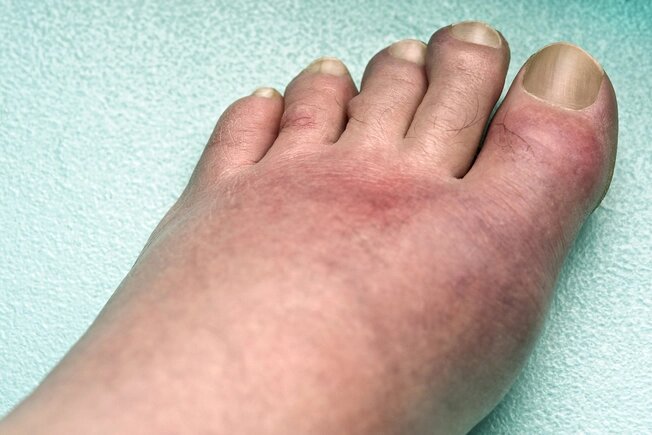

Gută

Sănătatea picioarelor este foarte importantă pentru menținerea mobilității la orice vârstă, așa că acest material va fi de interes pentru oricine îi pasă de picioarele lor.-10

10/17

Guta este o formă dureroasă de artrită, care este cel mai frecventă chiar și la mulți oameni de vârstă mijlocie; pe măsură ce înaintați în vârstă, riscul de a dezvolta depuneri de cristale purine în articulații crește. Acest lucru se întâmplă atunci când un produs rezidual din metabolismul nostru (acidul uric) se adună sub formă de cristale, adesea în articulațiile degetului mare. Poate deveni umflat, strâns și foarte dureros. Medicul dumneavoastră vă poate prescrie medicamente pentru a reduce umflarea. În aproximativ o zi te vei simți mai bine. Faceți exerciții fizice, mâncați mai puțină carne roșie și crustacee, limitați băuturile alcoolice și alimentele zaharoase și beți multe lichide pentru a preveni atacurile viitoare; s-a demonstrat că apa potabilă la muște prelungește viața creaturilor care suferă de boli asemănătoare gutei cauzate de defecte genetice.